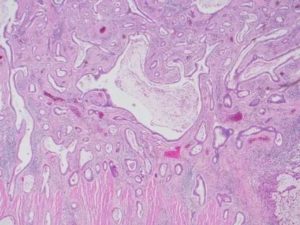

- Гистология опухолевой ткани выясняет природу новообразования. Завершающее исследование для постановки диагноза.

Диагностирование опухолевого процесса мало, чем отличается от других форм легочных онкологий и включает в себя на первом этапе рентгенографию, затем назначается КТ, визуализация проводится с помощью бронхоскопии. Окончательный диагноз ставится после обработки биоматериала.

Визуализацию опухоли при центральной локализации аденокарциномы производят с помощью бронхоскопии. При мелкобронхиальном росте с помощью бронхофиброскопа можно взять биоматериал для цитологического обследования бронхов.